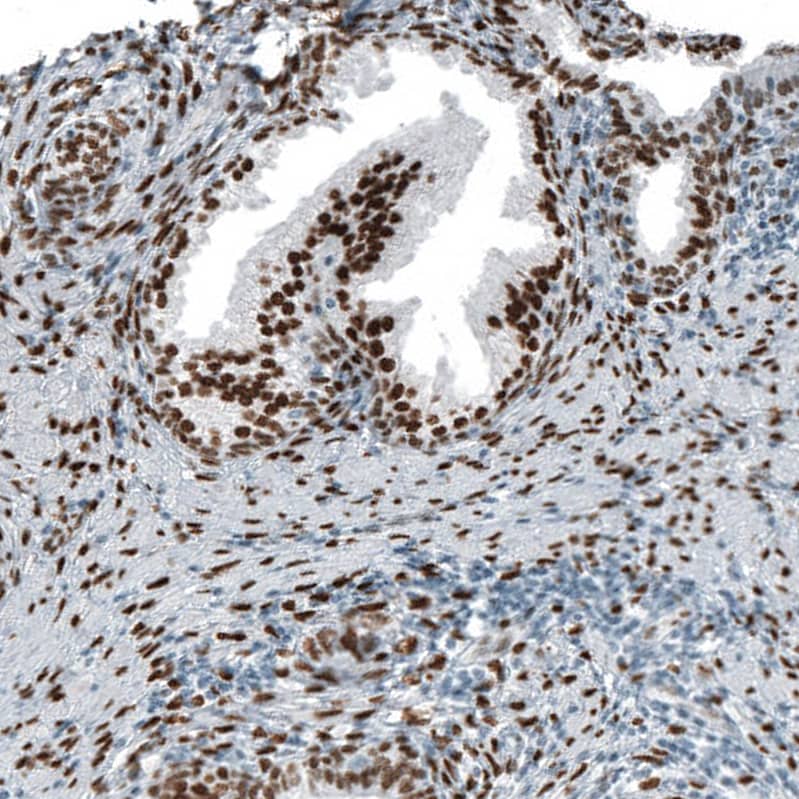

Staining of human breast cancer shows strong nuclear positivity in tumor cells.